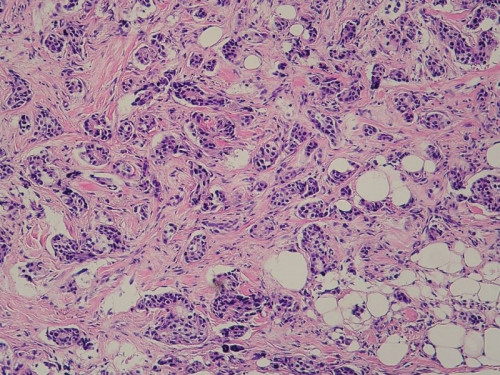

45 Jahre Frau. Sie tastet einen verschieblichen Mammatumor rechts. Das Ergebnis der durchgeführten Mammografie ist: BI-RADS IV.